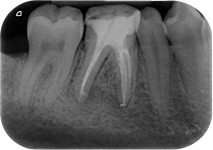

Ritrattamento Premolare

Visualizza caso clinico completo